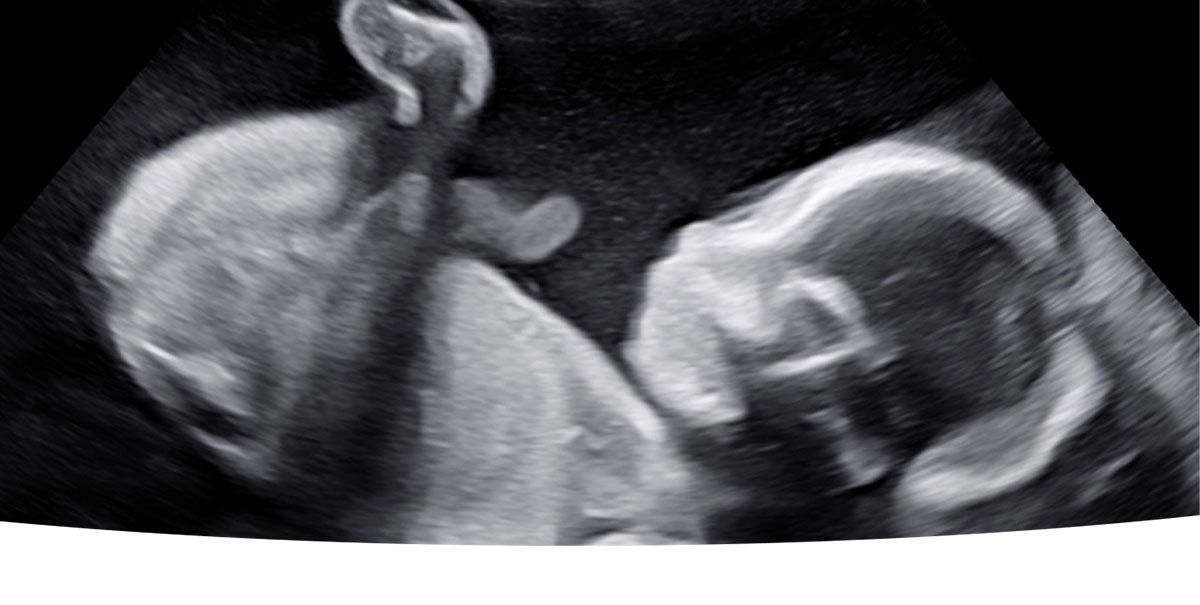

Ultralyd er lydbølger med så høj frekvens, at de ikke kan høres af det menneskelige øre. Man kan heller ikke mærke lydbølgerne. Lydbølgerne reflekteres af det væv de rammer og ved hjælp af avanceret udstyr dannes et billede på skærmen. Ultralydsscanning af gravide har været anvendt siden midten af 1960´erne og der er aldrig fundet tegn på skadelige virkninger – hverken hos fostret eller den gravide.

Du har mulighed for at læse meget mere om de scanninger vi tilbyder i 2D og 3D/4D scanning her på hjemmesiden. Hos Den lille jordemoder er det essentielt, at alle føler sig velkomne og trygge. Derfor er der afsat god tid til alle scanninger, således der er tid til at svare på de spørgsmål i eventuelt har om barnet eller graviditeten generelt.